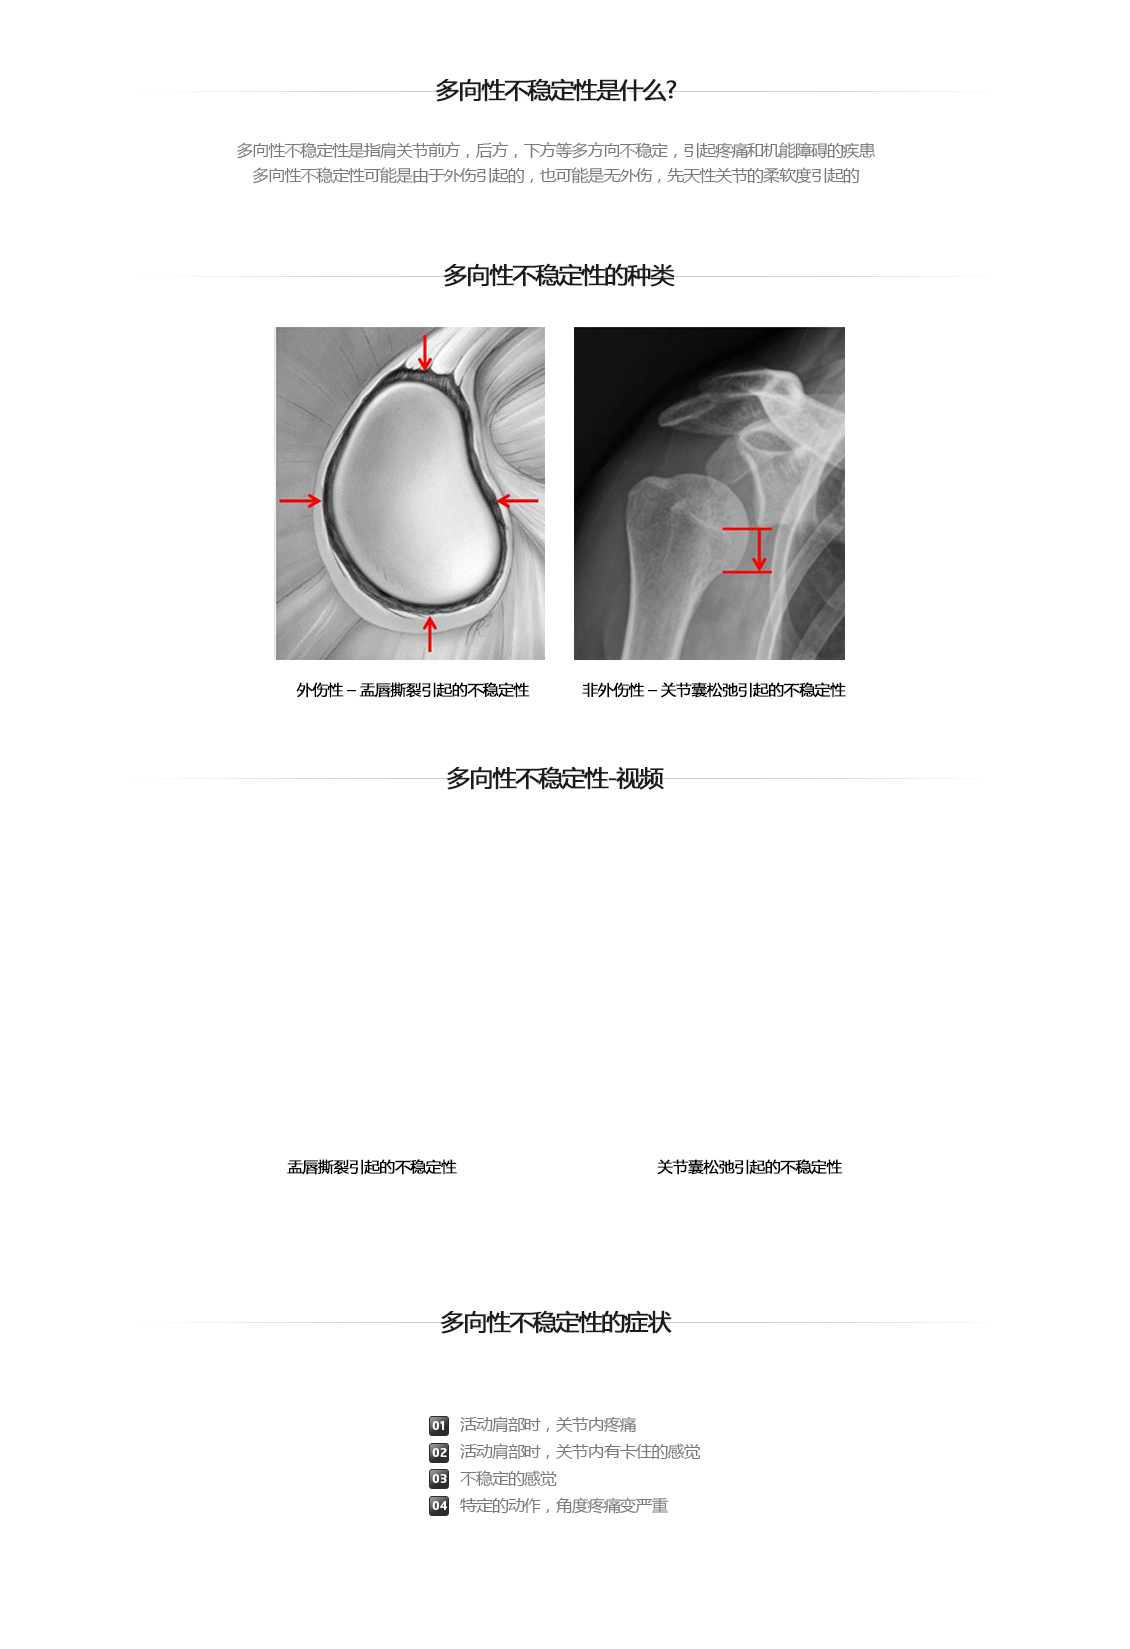

다방향성 不稳定性